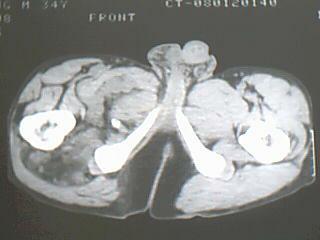

患者 男 34岁 右腿肿物。98年右侧外伤致股骨骨折,手术治疗,2001年二次手术(取钢板),发现大腿内侧有鸡蛋大小样肿块,无明显疼痛不适,2007年开始发现肿物明显增大,无发烧,无红肿。

病灶巨大,内见脂肪影,考虑软组织肿瘤,脂肪肉瘤?恶性纤维组织细胞瘤?

右侧大腿内侧肌间含脂性巨块,密度不均,内见软组织成分及条管状钙化,错构瘤伴出血?真性或假性脂肪瘤

病灶位于玉要位于肌间隙内,有大量脂肪结构,内可见网状条索影,病灶与内侧股群境界不清,如果其外伤有关首先考虑局限性淋巴回流不良引起的象皮肿样组织增生.其次考虑错构瘤,脂肪瘤或脂肪肉瘤等